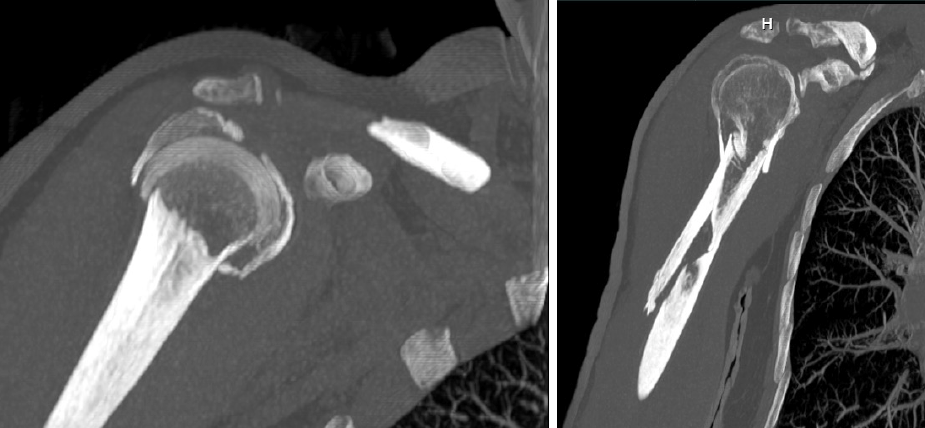

FRACTURA DE MIEMBRO SUPERIOR

Incluyen fracturas de clavícula, húmero, codo, antebrazo y muñeca. Muchas se tratan con yeso o férula, pero las desplazadas o graves requieren cirugía para fijar los huesos y recuperar la fuerza y la movilidad.